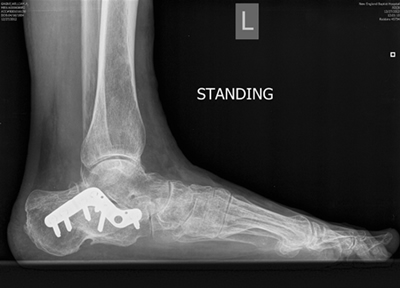

The pre-surgery x-ray from 2012 documents Bill's existing condition when he first visited Dr. Leavitt. It depicts a previous orthopedic surgeon's attempt to fix a calcaneal fracture. The plate was used to keep bone fragments together, but the surgeon was never able to restore the fragments to their correct position, and the plate was "banging" into the ankle bone. Between the arthritis that formed in the wake of surgery, the lack of restored height, and the metal on bone pain, Gagne was in severe pain.